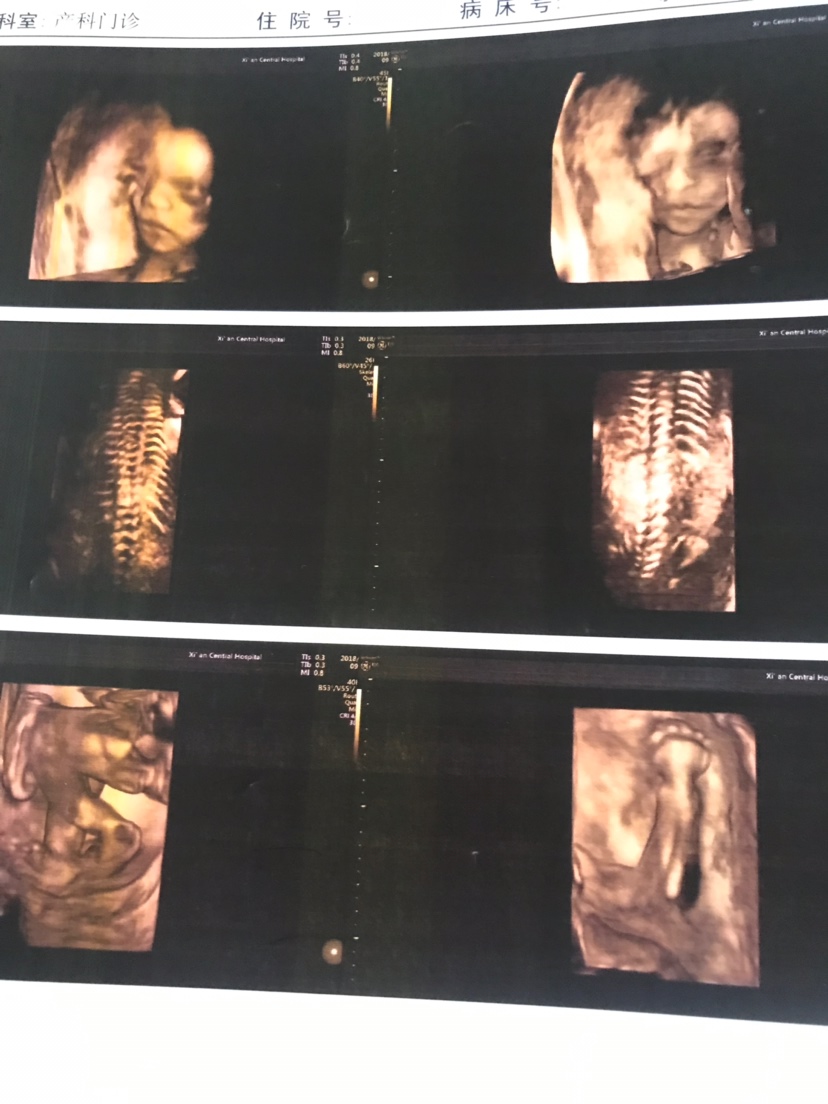

宝宝8个月20天

女宝